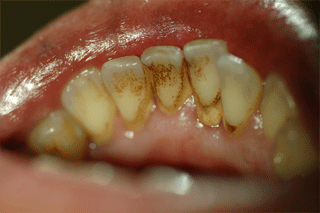

ひどい歯石

主な原因は歯についた歯垢(プラーク)です。歯肉近くに歯垢がたまると、歯肉に炎症が起こり、歯周ポケット(歯と歯茎の隙間)が広がります。

そうすると、歯茎から血や膿が出たして口臭を伴う場合があります。

さらに進行すると、歯根膜や歯を支える歯槽骨が溶け、歯がぐらつき、口臭がさらにひどくな ます。

最終的には歯がぐらぐらになり物が咬めなくなります。